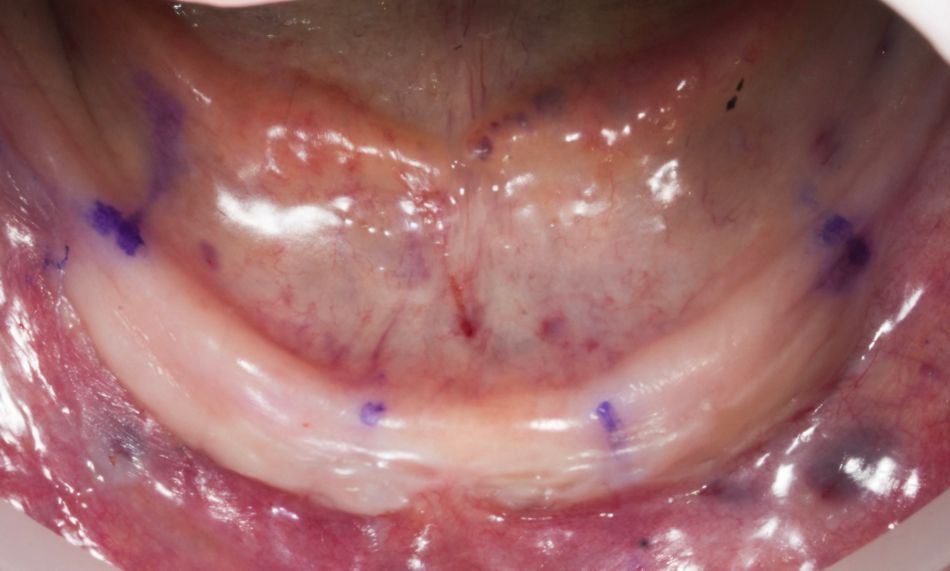

At the first appointment, a functional mock-up was fabricated to evaluate occlusion, esthetics, vertical dimension, and phonetics before proceeding with the definitive restoration (Fig. 15). The extraoral reverse scanning technique was used to digitally capture implant positions for prototype prosthesis fabrication. Three digital scans were acquired with an intraoral scanner (TRIOS 5, 3Shape). The first scan recorded the conversion prostheses in situ, capturing occlusal, palatal/lingual, and buccal surfaces, as well as the patient's occlusion. The second captured the soft tissue morphology of the arches with screw-retained abutments after prosthesis removal; and the third was an extraoral reverse scan of the prostheses with Straumann® RevEX™ scan bodies to accurately record the 3D implant positions and facilitate the design of the definitive prosthesis (Fig. 16).